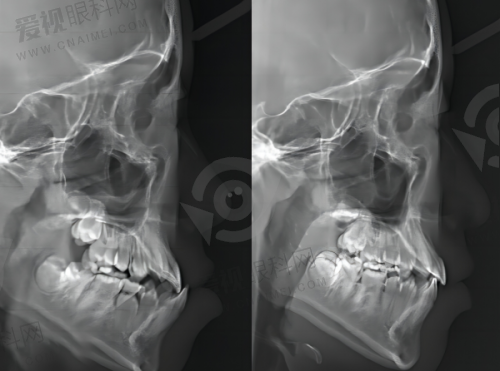

同时,门诊部还设有医学影像科,涵盖了X线诊断专精和CT诊断专精。医学影像在口腔疾病的诊断中起着至关重要的作用。X线诊断可以帮助医生清晰地看到牙齿的内部结构、牙根情况以及牙槽骨的状况,对于龋齿、根尖周炎等疾病的诊断具有重要意义。而CT诊断则能够提供更详细的三维图像,在口腔种植手术前,医生可以通过CT影像严谨地了解患者牙槽骨的密度、高度、宽度等信息,从而制定出更加精细的种植方案,提高种植手术的成功几率。

门诊部的医生首先为李先生进行了全方面的口腔检查,包括X线和CT检查。通过检查,医生发现李先生的牙槽骨条件较好,但由于门牙缺失时间较长,周围的牙龈组织有一定的萎缩。医生根据李先生的具体情况,制定了个性化的种植方案。